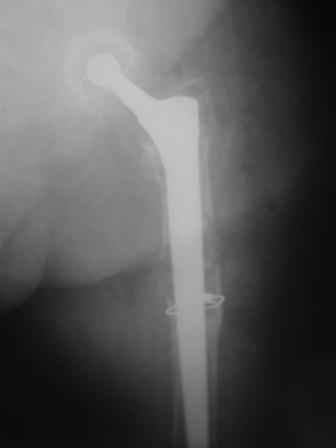

You transformed a cemented hip prosthesis to a cementless revision hip prosthesis with a little approach.

I generally should prefer a long stem revision prosthesis, as that allegated.

Bill Burman provided us with good references which show us that the topic is very hot, and the new option is being developed and evaluated. So it is too early to make final conclusion about its place and role.